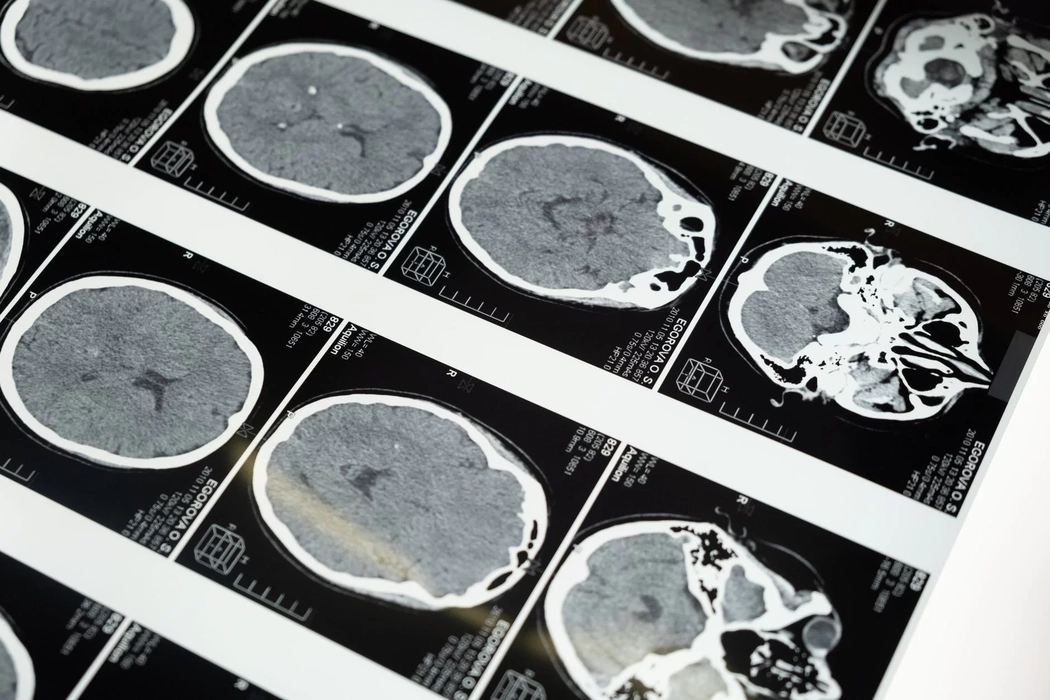

Cum se manifestă o atrofie cerebrală și cerebeloasă difuză? Iată câteva informații esențiale pentru înțelegerea afecțiunii!